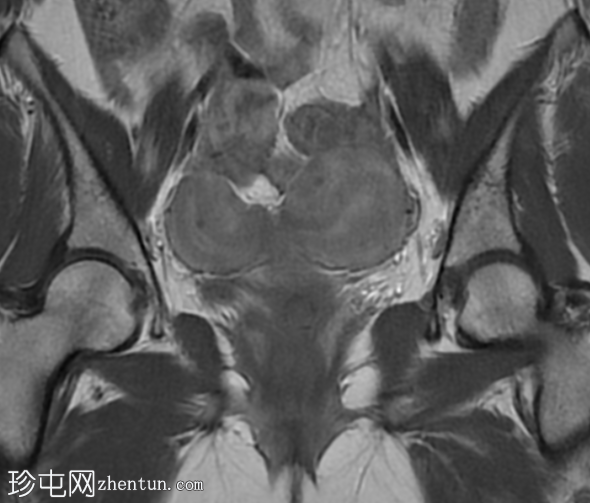

矢状位

T2加权像

双角子宫,有两个子宫角和一个宫颈(单颈双角子宫)

右角正常,分区解剖结构正常,无肌层病变

左角局灶性前壁腺肌症,前壁交界区边界不清,肌层内可见多个高信号灶

两个小的间质性肌瘤和一个大的浆膜下肌瘤

宫颈纳博氏囊肿

该病例表现为双角子宫单宫颈(双角单颈子宫),左侧单侧局灶性子宫角腺肌症,以及多发性子宫肌瘤。